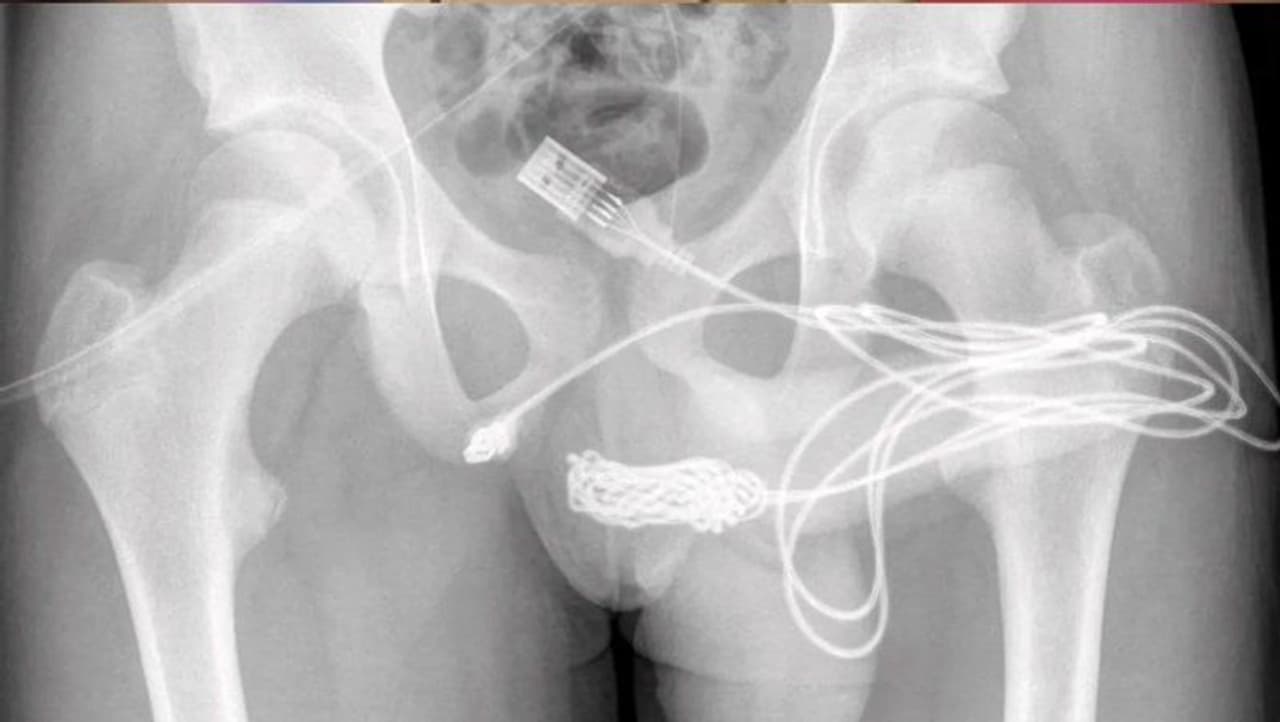

কীভাবে তারটি আটকে ছিল দেখুন

ইউরোলজি কেস রিপোর্টস মেডিকেল জার্নালের প্রতিবেদন অনুযায়ী, এরপর এক্সরে করে ওই কেবলের অবস্থান দেখেছিলেন ডাক্তাররা। সেটি ওই কিশোরের মূত্রনালীতে এমনভাবে আটকে গিয়েছিল, যে শল্যচিকিৎসকদের তার যৌনাঙ্গ এবং পায়ুর মধ্যবর্তী স্থানে আরেকটি ফুটো করে তারটি কেটে বার করতে হয়। পরে সেই জায়গাটি সেলাই করে বন্ধ করে দেওয়া হয়েছিল। মূত্রনালীতে একটি ক্যাথেটার ঢোকানো হয়েছিল। পরের দিনই তাকে সাধারণ ব্যথানাশক, অ্যান্টিবায়োটিক এবং ইউরেথ্রাল এবং সুপ্রাপিউবিক ক্যাথেটার দিয়ে ছেড়ে দেওয়া হয়েছিল। দুই সপ্তাহ পর চেক-আপ করে মূত্রনালীতে কোনও অস্বাভাবিকতা পাওয়া যায়নি। পরে ক্যাথেটারটিও সরিয়ে দেওয়া হয়। দীর্ঘমেয়াদী কোনও ক্ষতি হয়েছে কিনা তা পরীক্ষা করা হচ্ছে ফলো-আপ চিকিৎসায়।